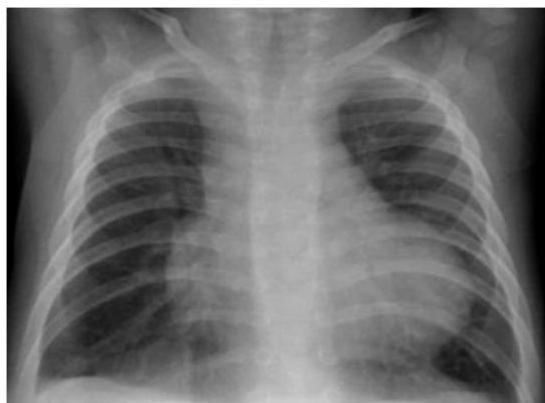

Preterm Infant with Respiratory Distress

- Preterm 29 weeks gestation C/S delivery showed severe respiratory distress soon after birth - RDS

- Air bronchograms

-

There is a homogeneous opacification of both lungs with white-out lungs - (1 .field (grounds glass appearance) and air bronchogram bilaterally

.The diagnosis is Acute Respiratory Distress Syndrome (ARDS) - (2

- .I- Massive blood transfusions Preterm 29-weeks gestation C/S delivery showed severe respiratory distress soon after birth. This chest x-ray was taken at the age of 6 hours.

- Q1: Write 2 abnormalities in the X-Ray?

- Q2: What is the likely diagnosis?

- Q3: Write 2 management steps.

Answers:

- Q1: Ground glass appearance, wide intercostal space.

- Q3: Mechanical ventilation, give Surfactant for lungs maturation.

What are the possible diagnoses? Congenital pneumonia or respiratory distress.

Respiratory Distress Syndrome (Premature Neonate)

X-ray? Ground glass appearance of the lungs with air bronchogram.

Diagnosis? Respiratory Distress Syndrome.